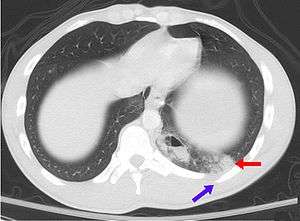

Asymptomatic conditions may not be discovered until the patient undergoes medical tests (X-rays or other investigations). Some people may remain asymptomatic for a remarkably long period of time; such as people with some forms of cancer. If a patient is asymptomatic, precautionary steps must be taken.

- Pulmonary contusion